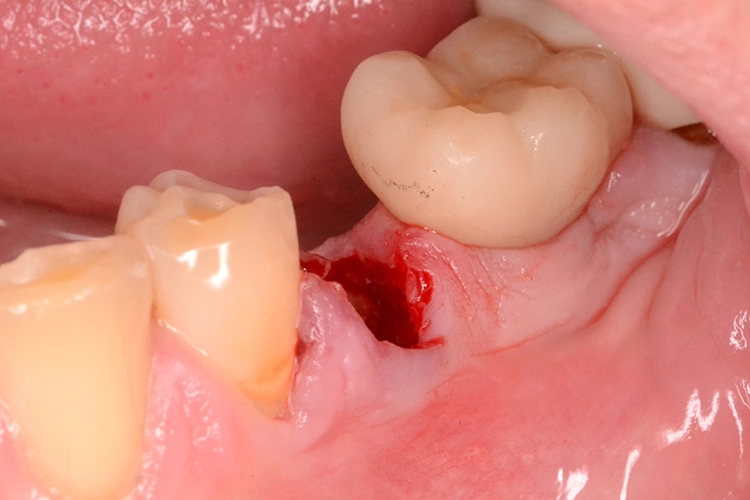

Grundvoraussetzung für eine Sofortimplantation stellt die minimal-traumatische Entfernung des Zahnes bzw. Zahnrestes dar. Dafür können beispielsweise besonders schonende Desmotome, wie z.B. die X-Tools der Firma Helmut Zepf oder die Piezosurgery oder auch der Benex-Extraktor der Firma Helmut Zepf zur Anwendung kommen.

Anschließend muss die Extraktionsalveole gründlich gereinigt werden. Hier ist es der Vorliebe des Behandlers überlassen, welche Maßnahmen er vornimmt. Von einem Anfräsen der Alveole bis hin zur Anwendung von Ozon, Laser oder H2O2 wird vieles praktiziert.